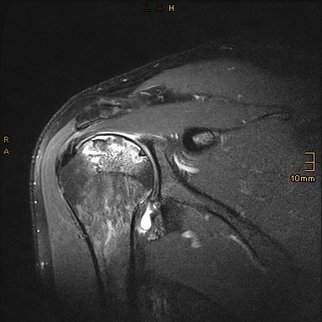

Die Prognose der rheumatoiden Arthritis hat sich in der letzten Zeit durch Einsatz neuerer Medikamente und standardisierter Therapien deutlich gebessert. Das Ziel der Therapie ist dem Betroffenen eine möglichst normale Lebensqualität zu bieten, auch wenn eine Heilung der Erkrankung nicht möglich ist. Die rheumatoide Arthritis (RA) ist eine destruktive Erkrankung. Kennzeichen ist eine progrediente Zerstörung der intra- und periartikulären Strukturen durch die entzündlichen Proliferationen des Gelenks und der umliegenden Weichteile. Sonographie und Schnittbildverfahren ermöglichen frühzeitig die Diagnosestellung bevor erste radiologische Destruktionen erkennbar werden. Zusammen mit der Bildgebung und den Symptomen helfen spezielle Laborparameter um die Diagnose „Rheuma“ einordnen zu können.

Schon in frühen Krankheitsstadien lassen sich ausgedehnte entzündliche Veränderungen der subakromialen Schleimbeutel, Entzündungen der langen Bizepssehne und Rotatorenmanschettendefekte (RMD) nachweisen. Dabei machen Ausdünnungen und Teilrupturen der Sehnen den Großteil der Defekte aus. Vollständige Defekte  liegen laut Literatur bei 20-40%. Der Anteil nicht rekonstruierbarer RMD wird zwischen 10 und 20% beschrieben.

Therapierefraktäre Synovialproliferationen sowie RMD sind heutzutage Domäne der arthroskopischen Chirurgie. Die subacromialen sowie intraartikulären Pathologien des Schulterglenks samt langer Bizepssehne und Rotatorenmanschette lassen sich über die Schlüsselloch-Technik versorgen. Die Vorteile der arthroskopischen Technik liegen in der geringeren Traumatisierung und geringeren Infektgefährdung, da wichtige schulterstabilisierende Sehnen und Muskeln sowie die Gelenkkapsel nicht abgelöst und wieder vernäht werden müssen. Der Zeitpunkt der Indikationsstellung sowie der Zustand der Weichteile, insbesondere der funktionellen Integrität der RM, bestimmt die Langzeitprognose. Je früher die operative Versorgung einer Pathologie erfolgt, desto besser sind die funktionellen Ergebnisse.

Im Langzeitverlauf entwickelt sich eine sekundäre Arthrose des Schultergelenks. Nicht selten werden auch in frühen Erkrankungsstadien unter systemischer und intraartikulärer Kortikoidtherapie uni- und bilaterale Humeruskopfnekrosen beobachtet. In diesen Fällen ist die Schulterendoprothetik die Therapiestrategie an der Schulter. Die Implantatwahl richtet sich nach dem könöchernen und weichteiligen Zerstörungsausmaß des Gelenks. Unsere modernen Schulterprothesen verfügen über eine modulare Bauweise. Verschiedene Kombinationsmöglichkeiten ermöglichen eine individuelle Rekonstruktion ihres Schultergelenks um die Biomechanik der schulterabhängigen Muskulatur wiederherzustellen. Auch hier lauten die primären Zielsetzungen die Schmerzreduktion und ein damit verbundener relativer Funktionsgewinn der aktiven Beweglichkeit.